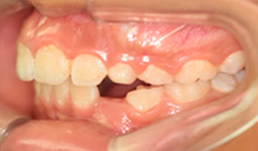

EJEMPLOS:

A) Maloclusión por mandíbula pequeña.

B) Maloclusión por mandíbula grande.

Mi hijo presenta ese problema si maxilar inferior es más pequeño

Hola Sonia, no te preocupes que este tipo de problema se puede corregir (las ultimas fotos del articulo es de una paciente nuestra de 7 años, antes y despues del tratamiento), mientras más temprano mejor. Cuentanos que edad tiene tu hijo. Te estaremos enviando por correo un articulo que publicaremos mañana para que puedas identificar otras características asociadas a maloclusiones, ya que estas nos permiten identificar que otros componentes funcionales están afectando el correcto desarrollo de los maxilares. Revisas el articulo de mañana y nos comentas. Saludos

Hola Vanesa, cualquiera de los casos de las fotos, son casos complejos, que usamos para que se hagan una idea de las maloclusiones, pero desafortunadamente lo que te dijo mi colega no es cierto, los maxilares nunca se emparejan este tipo de maloclusiones, al contrario empeoran con el tiempo y cuando son más grandes la única opción que generalmente queda es la cirugía de los maxilares. En el articulo puedes ver las fotos finales es de una paciente nuestra de 7 años que corregimos una severa maloclusión en casi 1 año, son fotos de la misma paciente antes y después. Si deseas una consulta déjanos tus datos y te podemos llamar para coordinar una cita. Espero tus comentarios. Saludos.